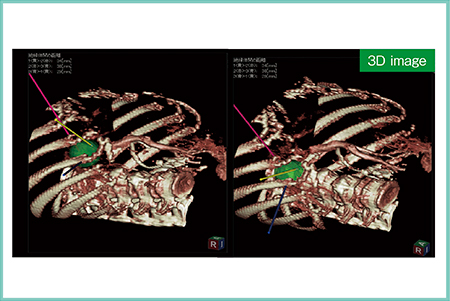

症例2は,82歳,男性。肝S5に4.5cmの肝細胞がんが認められ,TACE併用にてバイポーラ4cm針3本によるRFAを施行した。3本の電極針は,いずれも異なる肋間から穿刺して焼灼可能であり(図3),治療後のCTにて十分なマージンが確認できた。

図3 症例2:肝細胞がん症例へのTACE併用バイポーラRFA